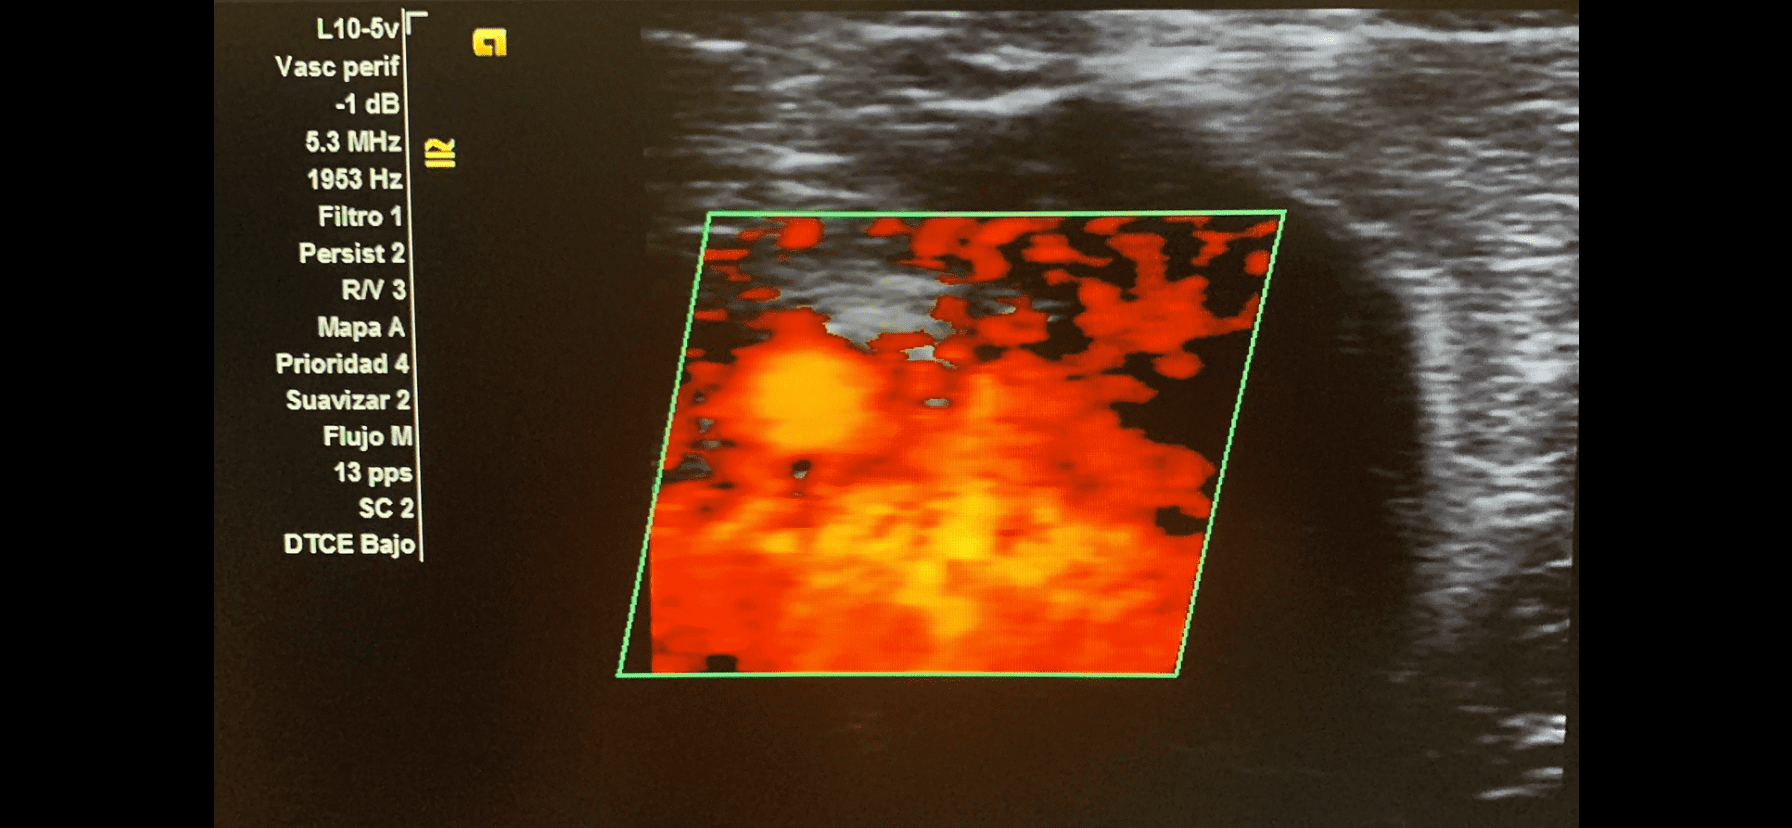

Imagen 3. Tono pulsátil de la fistula arteriovenosa.

AngioTC miembro inferior derecho: arterias femoral común, profunda y superficial permeables, de calibre normal, sin estenosis. Gran fístula arterio-venosa en tercio medio de femoral superficial, de alto flujo.

Gran fístula arteriovenosa de alto flujo en tercio medio de femoral superficial de miembro inferior derecho.